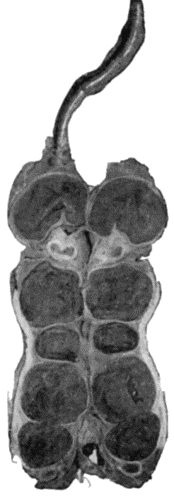

| 118. | Shaft of the Femur after Acute Osteomyelitis | 444 |

| 119. | Femur and Tibia showing results of Acute Osteomyelitis | 445 |